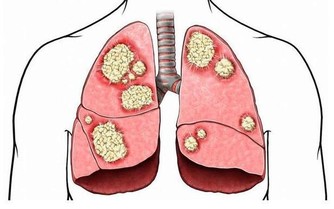

惡性黑色素瘤是皮膚癌的一種,雖然在中國還不是很常見,但是在歐美地區卻是常見的惡性腫瘤之一。在我國不常見並不意味著黑痣對人體是無害的,近幾年來皮膚癌在我國的發病率也逐漸升高,所以我們還是需要了解其產生的原因,事先做好防護措施,防患於未然。